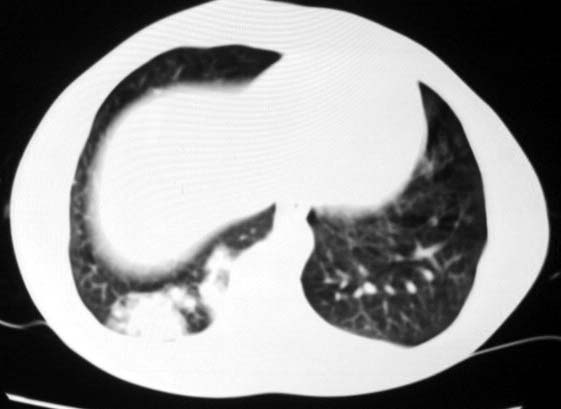

标题: CT5614:外伤病人男,20岁,右上腹痛.余肺野(-) [打印本页]

标题: CT5614:外伤病人男,20岁,右上腹痛.余肺野(-)

如果与外伤有关的话应该考虑右下肺挫伤.

最后一幅图像病灶区可分椎旁肋骨骨折可能?请示骨窗,结合外伤史考虑右下肺挫伤。

其次,病灶较多并散布在右下肺底,纵肺比例明显小于50%,与膈肌以及后壁胸膜有轻度粘连。且其内密度不均匀,最大的那个结节影里面有较致密密度,胸椎旁似乎还有液平面。也就是说右下肺炎性改变可以肯定。

但下肺毕竟不是结核的好发部位,而且病灶形态、密度也不怎么符合,我大胆猜测一下:因为右侧主支气管较左侧短而直,如果有异物容易掉落入右肺。更因为重力关系容易进而掉入右下叶支气管,继而沉积在肺底引起炎症。这个诊断需要临床病史,建议楼主详细追问有无异物吸入史以及反复肺部感染病史,特别是有无米饭之类的异物吸入病史。

结合病史,应首先考虑右下肺挫裂伤,但也不能完全排除感染性病变。还需进一步询问临床症状!

外伤病人男,20岁,右上腹痛,ct显示:右肺下叶后基地段见斑片状高密度影,密度不均,边界清,考虑1,右肺下叶肺挫伤;2,炎症。

最后一幅图像示椎旁肋骨走形欠自然,请示骨窗,结合外伤史考虑右下肺挫伤。